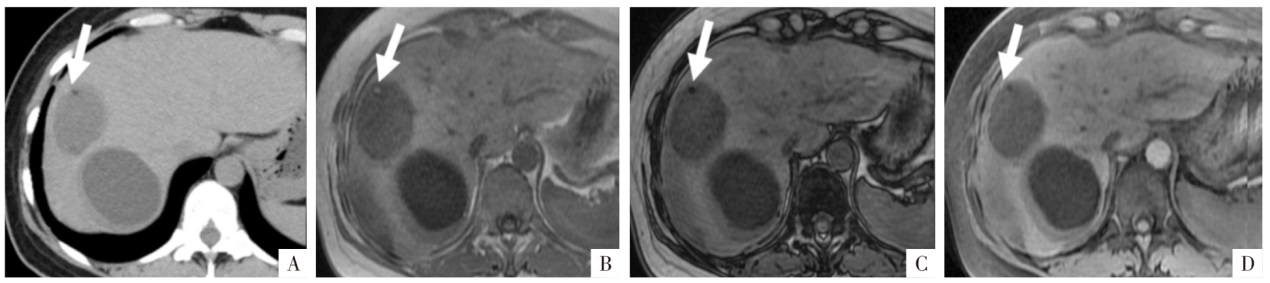

图1

含脂成分的CT与MRI表现。A图,病人女,47岁,肝S5段的血管平滑肌脂肪瘤。CT平扫病灶内可见低密度区域,CT值约为-79 HU,容易确认为脂肪组织。B-D图,病人男,69岁,肝细胞癌脂肪变性。白箭所指为脂肪变性区域,CT平扫上局部呈相对低密度(B),CT值约16 HU,但难以确定为含脂成分;T

1

WI同相位上相应区域呈现稍高信号(C),反相位上相应区域信号明显衰减(D),可以明确判断为脂肪变性。